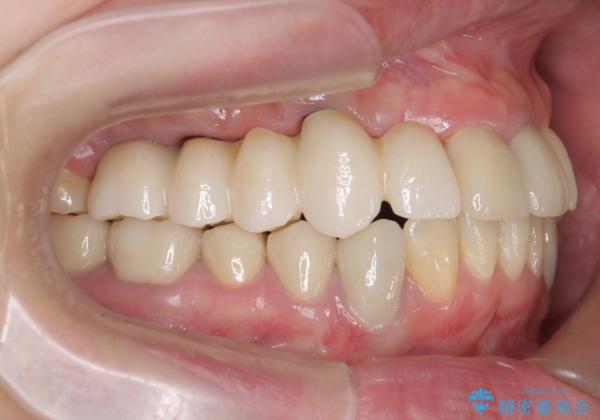

虫歯による多数歯欠損 インプラント咬合機能回復

- 虫歯が多発し、多数失ってしまった歯の審美性回復・機能回復を計画します。

多数の歯が失われておりブリッジは行えないような状況で、インプラント治療か入れ歯治療かを提案しインプラント治療を希望・選択されました。

- 120万円(ストローマンインプラント×3・骨造成・チタンカスタムアバットメント×3・フルジルコニアクラウン×5)費用は治療当時の料金となります